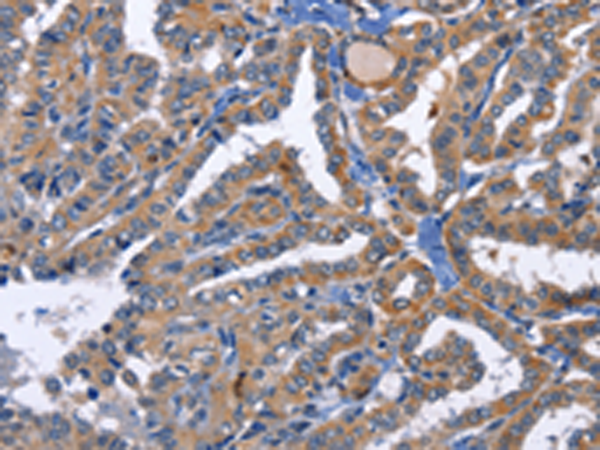

分类: 科研抗体货号: P07954别名: MAY1; PKCD; nPKC-delta应用: WB,IHC反应种属: Human, Mouse, Rat